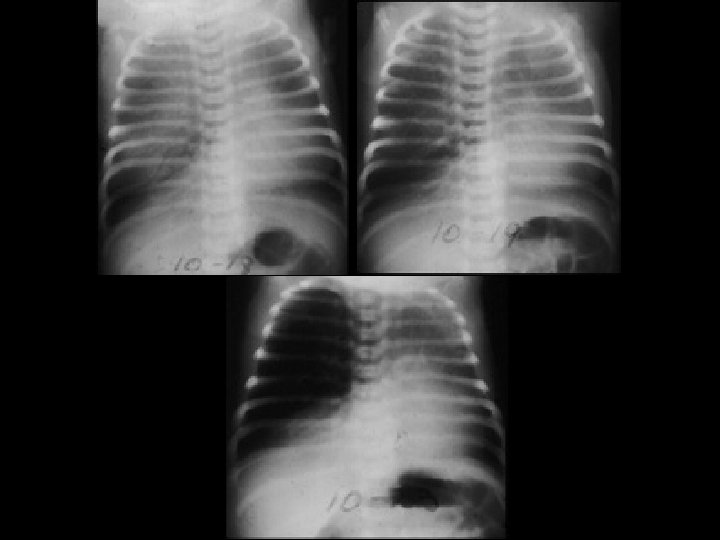

Meconium Aspiration • Findings: – coarse and patchy densities with areas of overinflation and peripheral air-trapping • Normal fetuses with prepartum distress and hypoxemia release meconium and aspirate it • ddx: – HMD – neonatal pneumonia – TTN